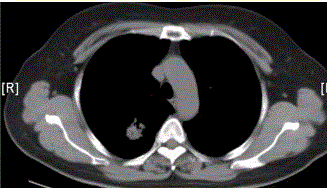

问题 患者女,54岁,无症状,常规体检透视时发现右上肺阴影。既往无结核病史。体格检查阴性。CT结果如下图。 最易出现分叶状边缘的肺癌类型是

选项 A.鳞癌 B.腺癌 C.未分化癌 D.肺泡癌 E.转移性肿瘤 F.肺类癌

答案 B